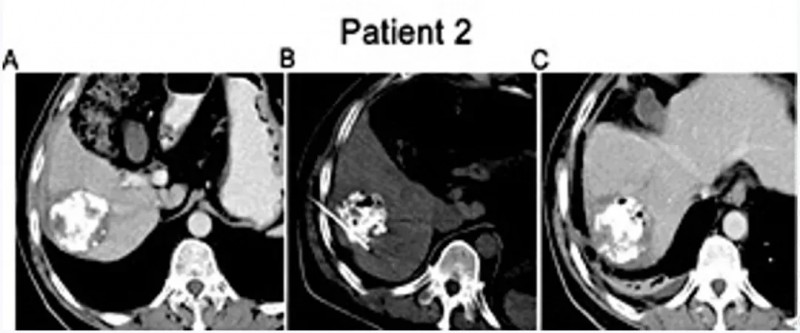

值得一提的是,一位52岁IV期肝细胞癌女性患者(患者2)的治疗效果尤为突出:初始HCC结节最大直径3.0cm(详见下图A),经IRE联合同种异体NK细胞治疗后,MRI显示病灶内出现大面积坏死(详见下图C)。

▲图源“Cell Physiol Biochem”,版权归原作者所有,如无意中侵犯了知识产权,请联系我们删除